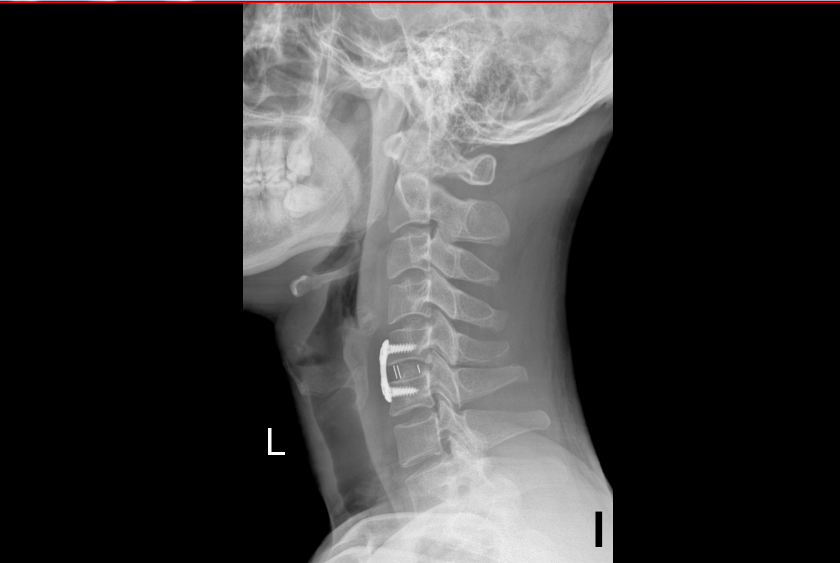

案例一术后

“经过颈椎磁共振检查,发现你的颈5/6椎间盘髓核突出压迫脊髓,并伴有椎管狭窄”,接诊的刘汝专主任说道。结合症状、体格检查和影像学检查,排除了颅脑问题后诊断陈先生为脊髓型颈椎病引起的下肢乏力和步态不稳。经科室讨论,刘汝专团队决定采用“颈椎前路颈5/6椎间盘切除+Cage植骨融合内固定术”治疗陈先生。

“这类手术方法在颈椎手术中属于比较经典的颈椎微创手术,它能够对颈椎间盘髓核突出压迫脊髓进行直接摘除减压,同时也可以通过椎间融合器植入恢复一定的颈椎生理曲度,而且术口一般长度约为3-4cm,愈合快出血量少”,刘汝专主任告诉陈先生和其家人。术后第一天,陈先生感觉自己的下肢“如释重负”,乏力症状明显改善,走路也比术前稳了很多,术后第七天术口拆线后就出院回家了。